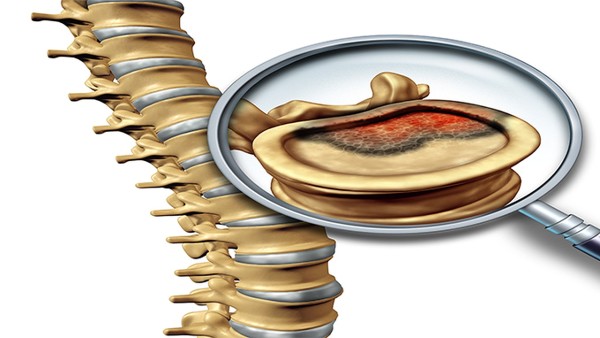

四肢骨折外固定后注意事项

四肢骨折外固定后,护理和康复是关键,直接影响恢复效果。外固定通常用于稳定骨折部位,帮助骨骼愈合,但固定期间需要注意很多细节,才能避免并发症并加快恢复。骨折后,外固定器或石膏会限制患肢的活动,目的是让骨骼在正确的位置愈合。固定期间,血液循环可能会受到影响,肌肉也可能因为缺乏活动而萎缩。如果不注意护理,可能会出现肿胀、疼痛、皮肤问题,甚至影响骨折愈合的速度。固定期间,保持患肢的清洁和干燥非常重要。石膏... ...